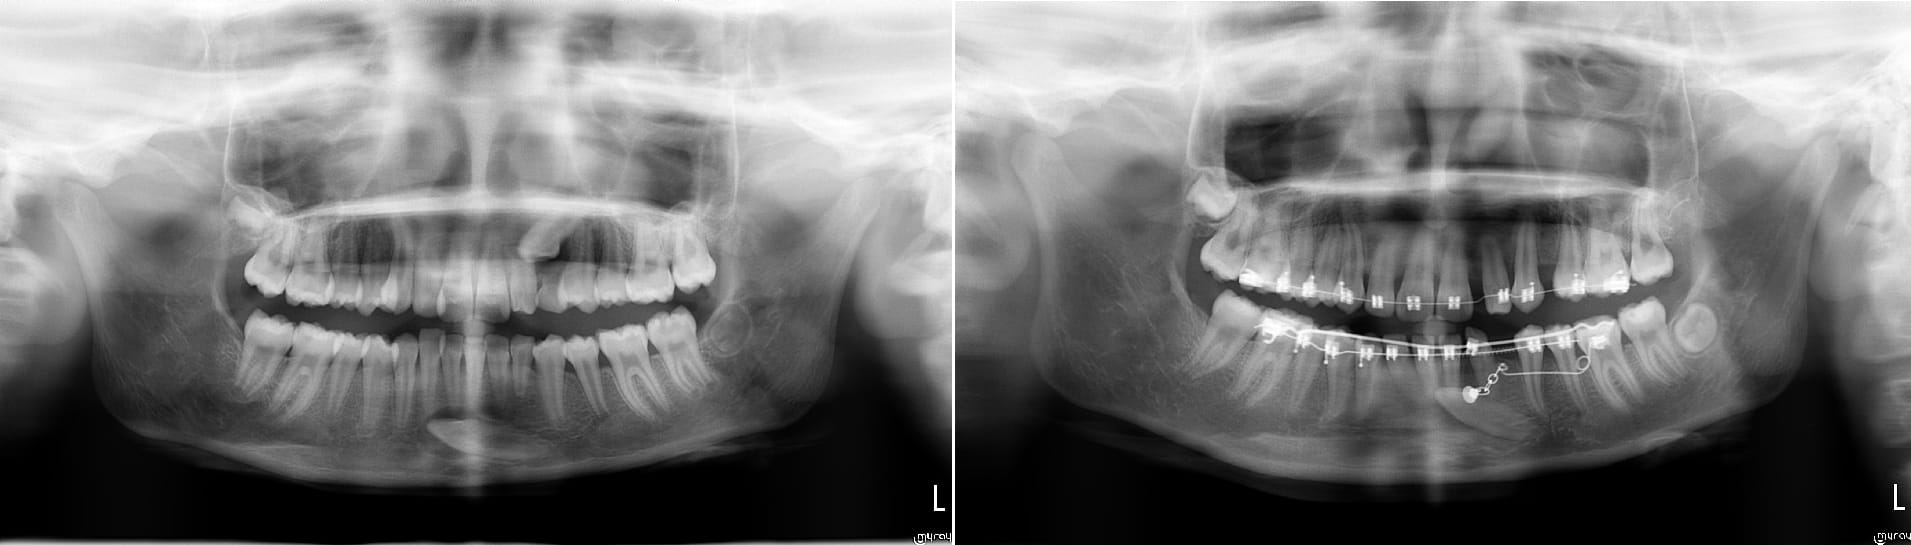

Possible, pas possible ?

L'apex de la 43 est en bonne position, ce qui veut dire que tu n'a qu'a faire un mouvement de tipping pour redresser la dent.

J'ai quasi le même cas en cour :-) .

La patiente avait besoins d'un traitement ortho ( une canine impacté en haut aussi ) donc j'ai intégré la traction avec l'appareillage et pas besoin d'utiliser de minivisse.

Par contre c'est long prévoir minimum un ans pour redresser la canine.

Plus d'un ans pour en arriver là.